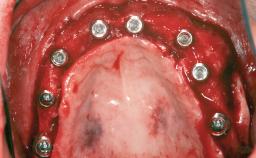

A 46-year-old woman was referred for treatment whose main complaints were mobility of her fixed partial dentures (right maxilla and left mandible) and periodontal bleeding during function. She also reported having taken systemic antibiotics to treat recurrent swelling in the area of the upper left molars. The patient had not seen a dentist for at least 2 years. She did not smoke and had no history of major systemic disease other than two minor orthopedic procedures some years back. The first-visit examination revealed poor plaque control, tooth mobility, periodontal disease, and a residual dentition widely associated with deep periodontal pockets.

Bone Augmentation Horizontal|Staged|Vertical

Augmentation Materials Autogenous chips|Autogenous block(s)|Xenogenous